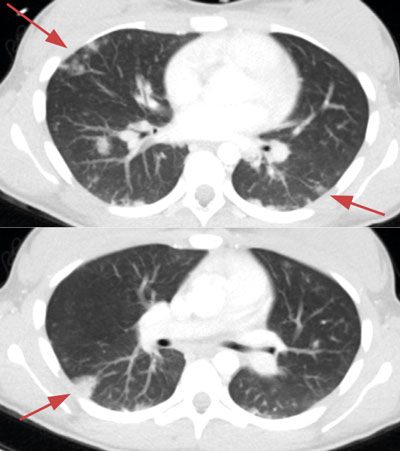

Initialt var diagnosen oklar, men på grund av misstanke om nekrotiserande fasciit i halsområdet gavs trippelbehandling med meropenem, klindamycin, och metronidazol. Tanken på Lemierres syndrom väcktes då datortomografi (DT) av hals och torax visade begynnande trombotisering av vena jugularis interna på vänster sida och embolisering till lungorna (Figur 1 och 2). Diagnosen bekräftades då blododlingar visade växt av Fusobacterium necrophorum i två av fyra flaskor. I svalget växte streptokocker grupp C eller G (slutlig speciesbestämning saknades). Anaerob odling utfördes inte då specifik frågeställning om F necro­phorum inte angavs. Serologin av Epstein–Barr-virus (EBV) visade på genomgången primärinfektion. Dalteparin gavs initialt men sattes ut då senare DT-undersökning inte visade progress av trombosen i jugularis­venen, men däremot tillkomst av pleuravätska (Figur 3). Flickan vårdades på barnavdelning från dygn sex. Där gavs behandling med bensylpenicillin och metronidazol intravenöst. Hon skrevs ut till hemmet med peroral klindamycinbehandling. DT-kontroll (hals, torax) i samband med återbesök en månad senare visade normala förhållanden, varför klindamycin avslutades. Hon mår nu bra.

Figur 2. Axiala DT-snitt visar spridda subpleurala förtätningar motsvarande septiska embolier.

Figur 3. Axialt DT-snitt visar tillkomst av pleuravätska dorsalt basalt intill ett par förtätningar.